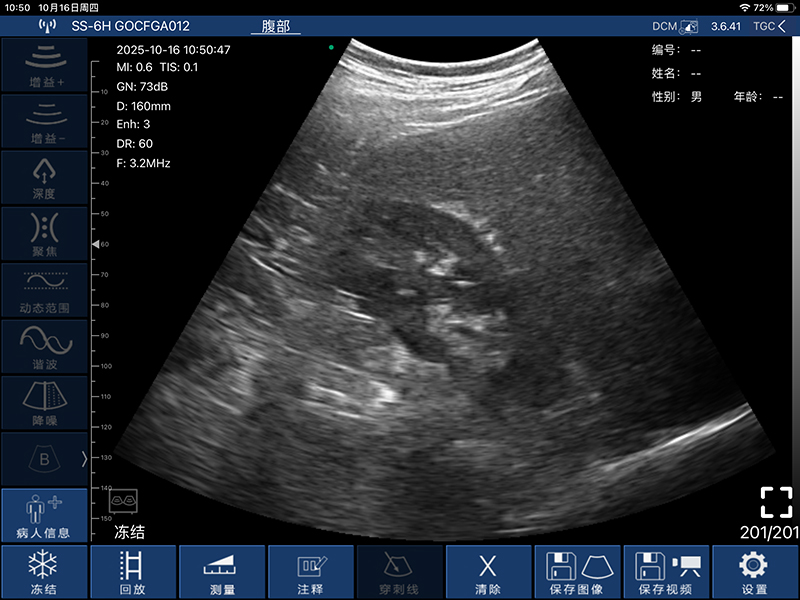

• 扫描方式:电子阵列扫描

• 探头频率:3.2/5.0MHz

• 扫描深度:90/160/220/305mm,可调

• 图像调节:增益、焦点、反相脉冲谐波、降噪